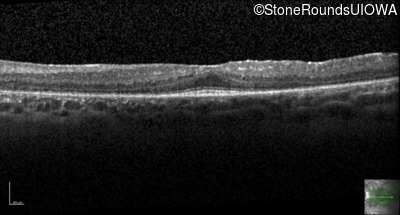

Optical Coherence Tomography - Right - 20/50

Exemplar / OCT Stack

OCT Stack